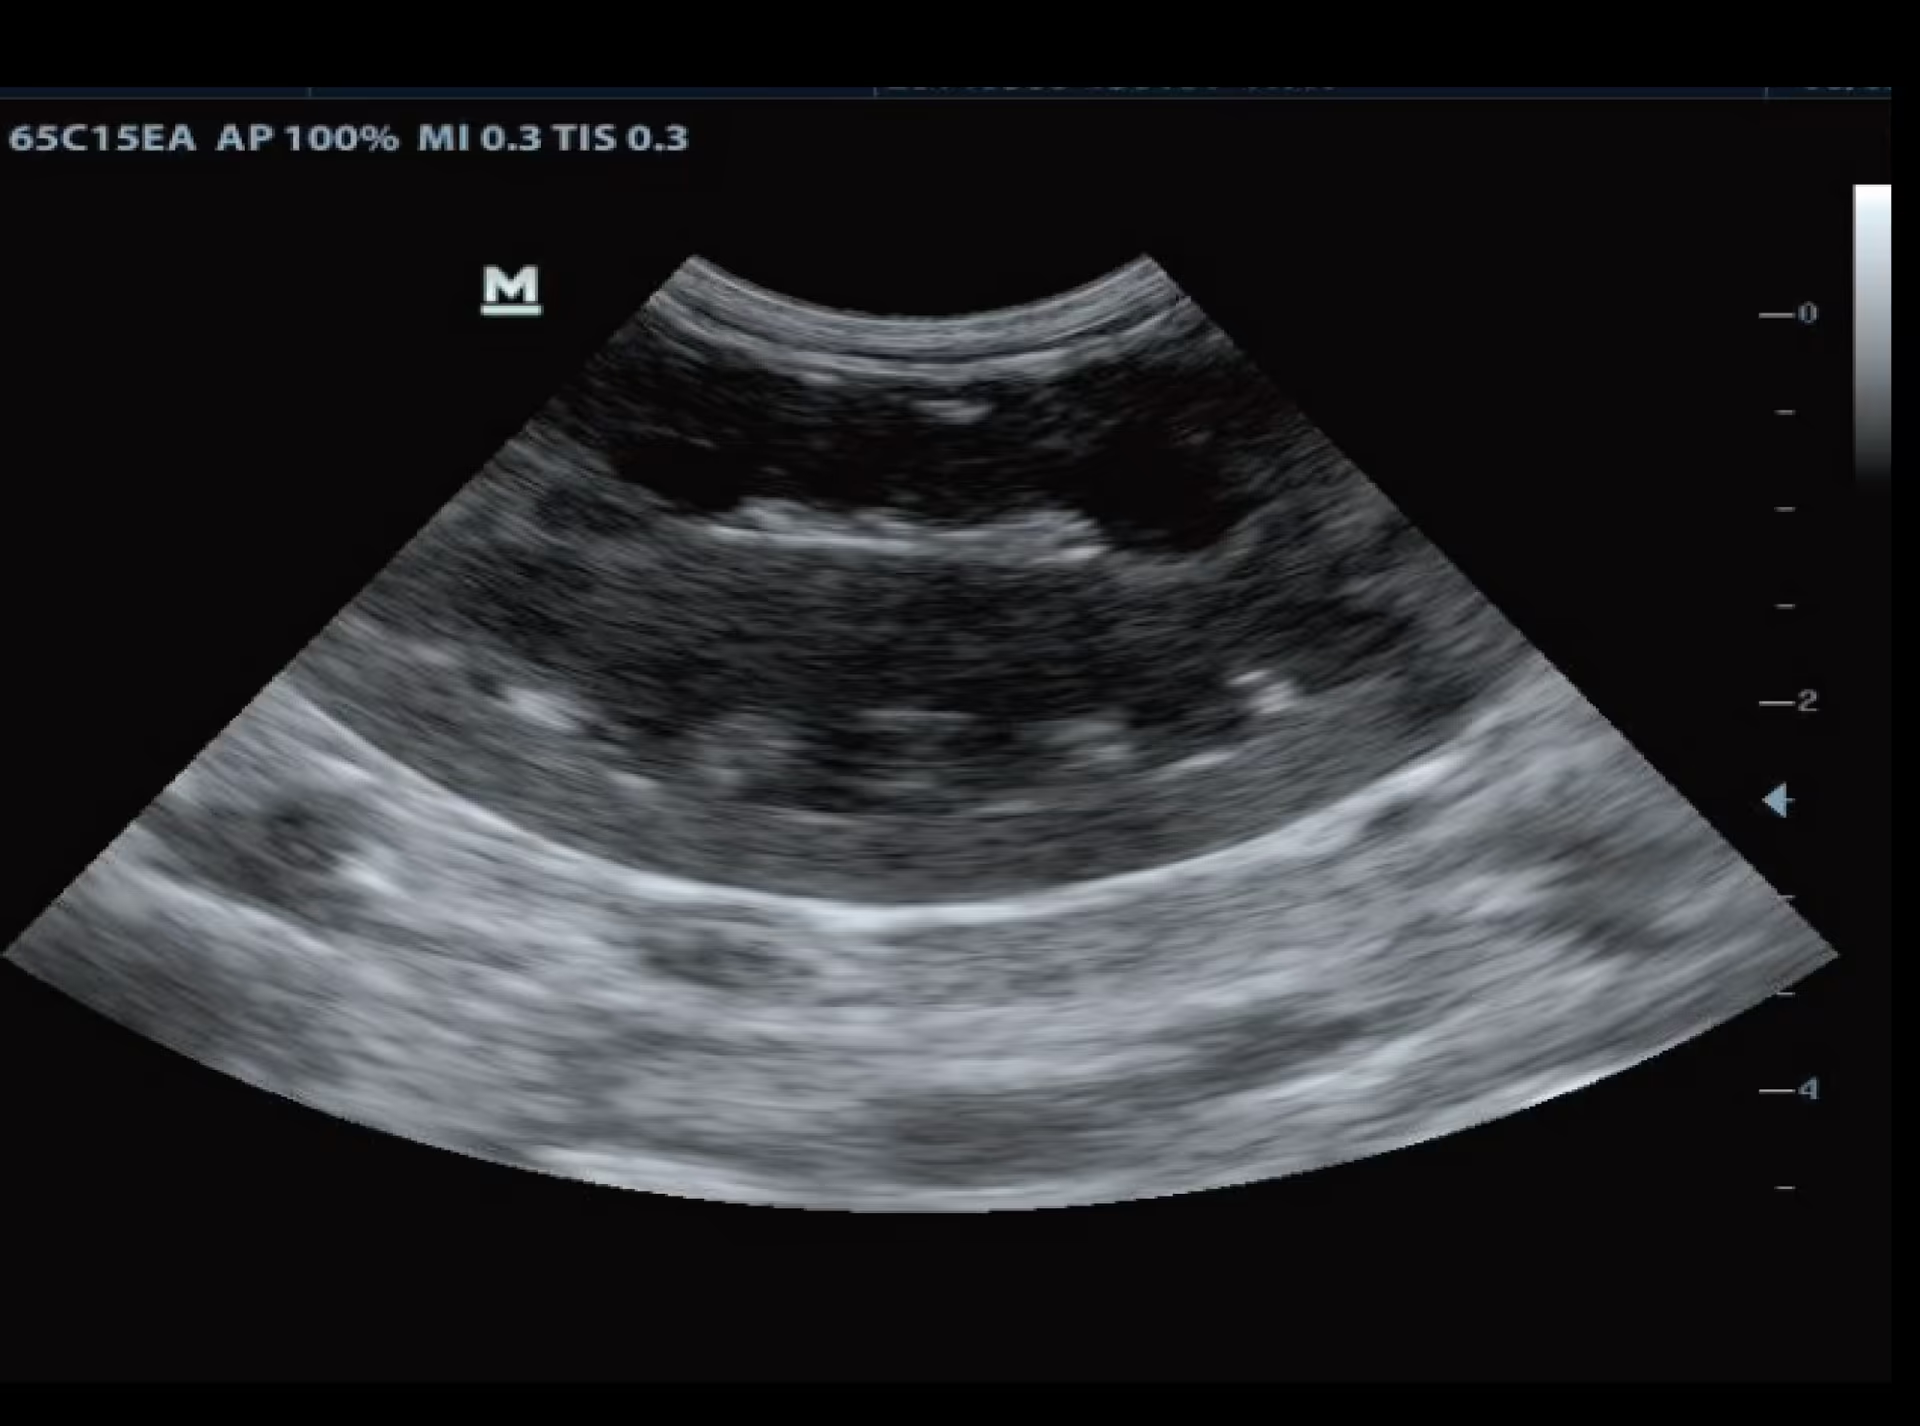

Böbrek, Kedi

Böbrek, Kedi